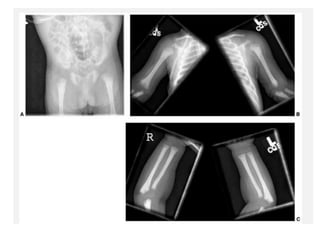

Multiple epiphyseal dysplasia. Radiographs of the hip (A), left knee

(B,C), left foot and ankle (D,E), and left wrist (F) show lack of epiphyseal

ossification centers with punctate calcifications in the knee.

Multiple epiphyseal dysplasia in an adolescent. AP and lateral radiographs of

the knee (A,B) and ankle (C,D) showing irregular epiphysis with joint deformities.